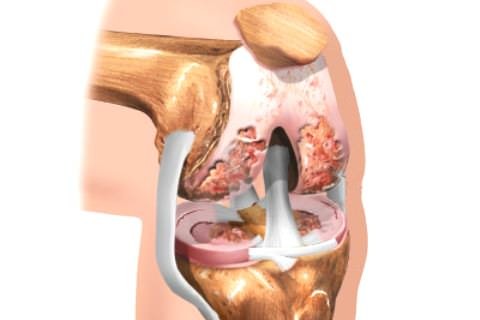

Остеоартрозом называют группу заболеваний суставного хряща и околосуставных тканей (рис. 1), в которых происходят дегенеративные нарушения. В основе остеоартроза лежит поражение гиалинового хряща, подлежащей (субхондральной) кости, синовиальной оболочки и капсулы сустава, околосуставных связок и мышц.

При остеоартрозе снижается плотность и эластичность хряща, происходит его истончение, разволокнение, растрескивание с образованием эрозий. Суставная поверхность прилежащей кости уплотняется и утолщается, суставная щель между хрящами сужается, формируются костные разрастания – остеофиты, похожие на шипы (рис. 2).

Они травмируют капсулу сустава, вызывая воспаление ее внутренней синовиальной оболочки (синовит). В результате возникает боль в суставе, он увеличивается и деформируется, а главное – не может полноценно работать.

Стадия остеофитов

Хрящи и мениски начинают разрушаться, боль возникает при обычной физической нагрузке и сама не проходит, снимается анальгетиками. Сустав увеличивается, нарушается его форма и подвижность. Размер суставной щели на рентгеновском снимке заметно уменьшен, видны явные костные разрастания. Поверхность сустава изменена (на снимке – просветления в кости).

Тяжелый артроз

Беспокоят постоянная боль, стойкая деформация суставов с нарушением оси конечности, резкое ограничение подвижности. Из-за вынужденного бездействия в определенных группах мышц развивается атрофия, может измениться длина конечности. При рентгенологическом исследовании суставная щель не визуализируется. Поверхность сустава изменена, видно обширное разрастание остеофитов, наблюдаются явные кистозные просветления в кости.